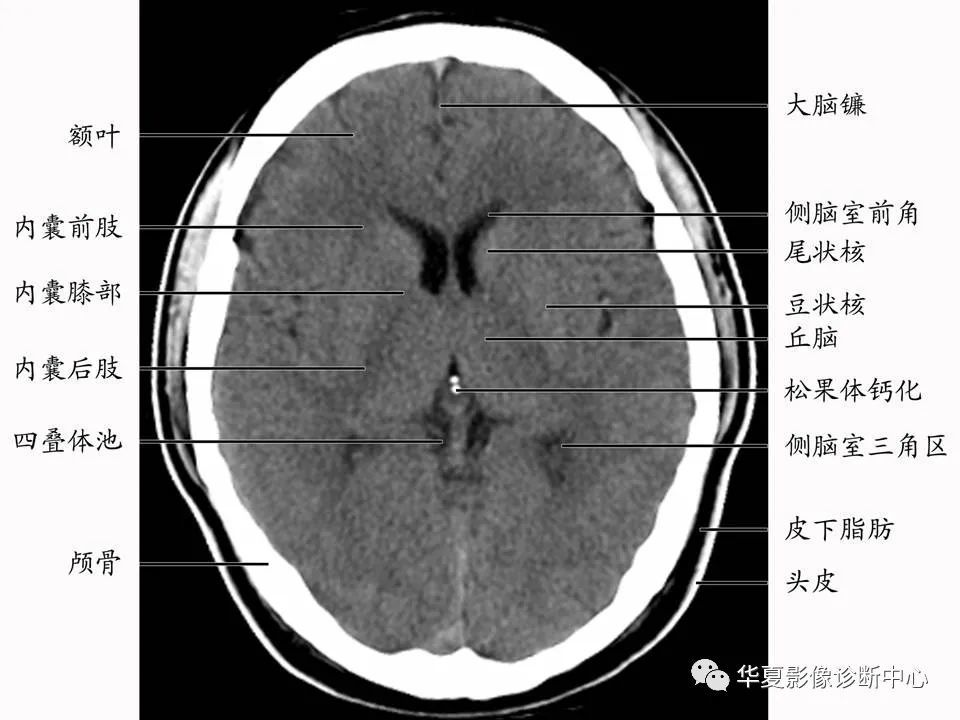

基底节层面

【影像基础】值得收藏的基底节及周围区域解剖详图